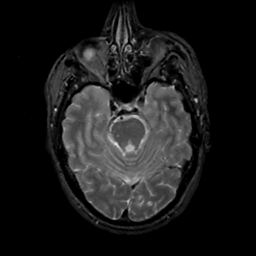

MR Study #12, May 12, 1991 -- Slice #16